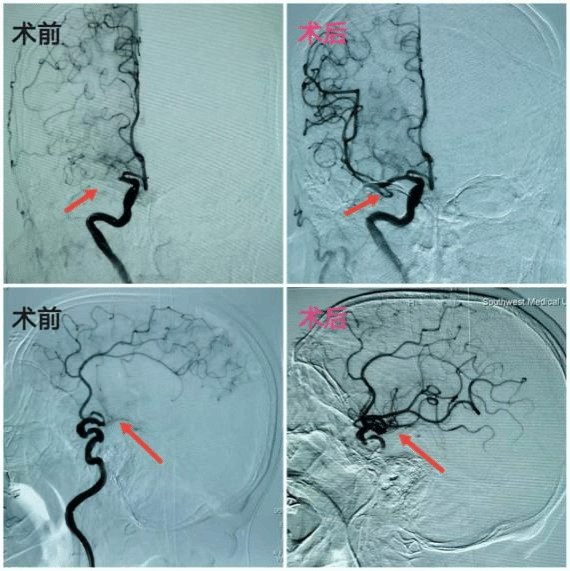

科室常规开展急性脑梗死静脉溶栓、颅内外动脉狭窄血管成型和支架置入术、急性脑卒中介入取栓、脑血管闭塞再通、动脉瘤血管内栓塞及覆膜支架植入术等介入技术。